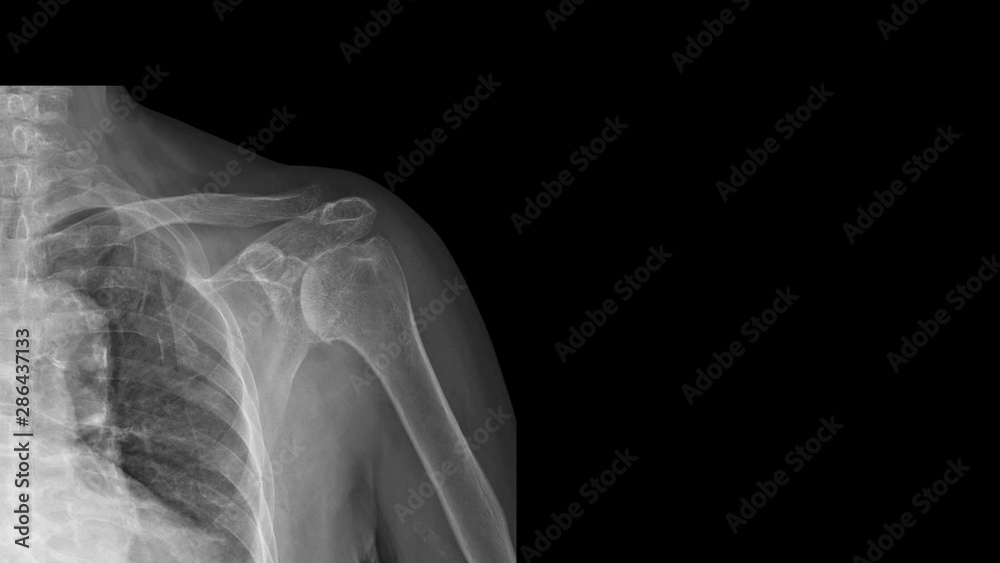

From stock.adobe.com

Film Xray shoulder radiograph show degenerative osteoarthritis disease X Ray Shoulder Osteoarthritis The diagnosis of shoulder osteoarthritis involves a specific set of symptoms, physical examination findings, and changes to the bone, which are. Tests that might be ordered to diagnose osteoarthritis of the shoulder include: Learn about the types of shoulder arthritis, including osteoarthritis and rotator cuff tear arthropathy, and the associated surgical and nonsurgical treatments. A doctor may also try to. X Ray Shoulder Osteoarthritis.

Film X ray shoulder radiograph show degenerative osteoarthritis disease X Ray Shoulder Osteoarthritis Blood tests, mainly to look for rheumatoid. The diagnosis of shoulder osteoarthritis involves a specific set of symptoms, physical examination findings, and changes to the bone, which are. Learn about the types of shoulder arthritis, including osteoarthritis and rotator cuff tear arthropathy, and the associated surgical and nonsurgical treatments. Tests that might be ordered to diagnose osteoarthritis of the shoulder. X Ray Shoulder Osteoarthritis.